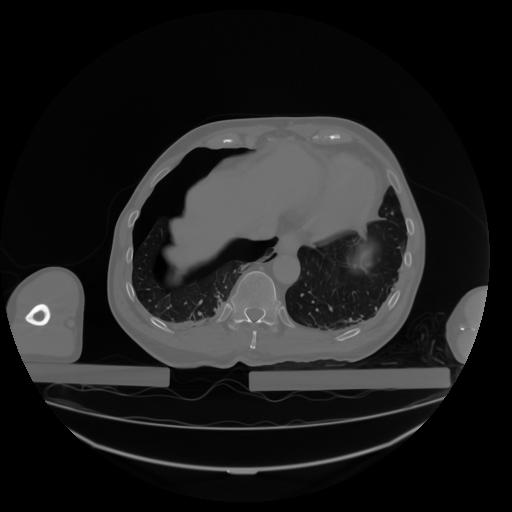

27 CUERPO,CE,Axial,3.0,CUERPO,,